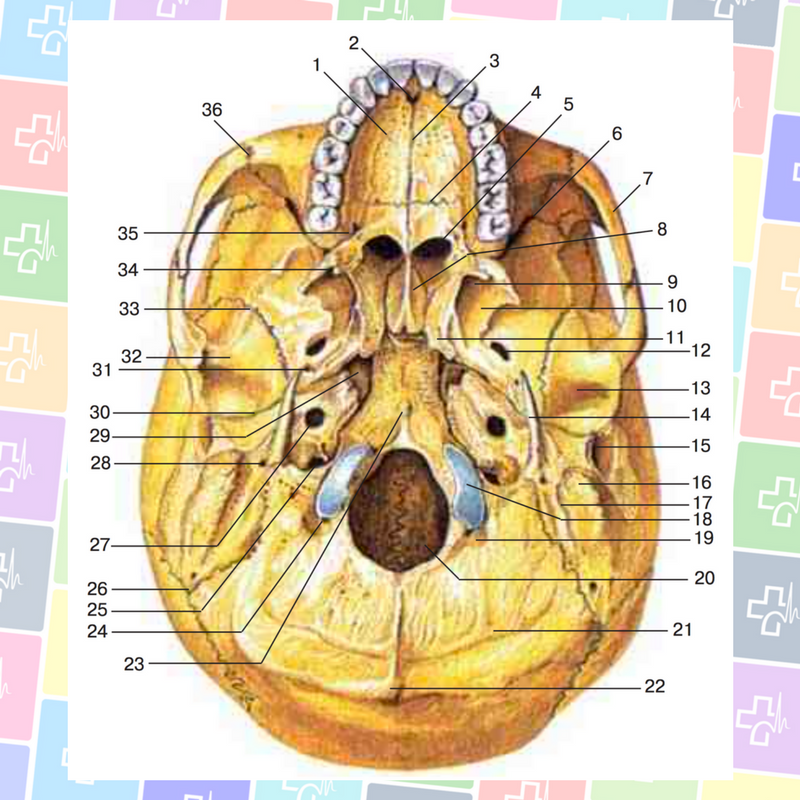

Анатомические детали: Фотографии топографии черепа с нижнего вида